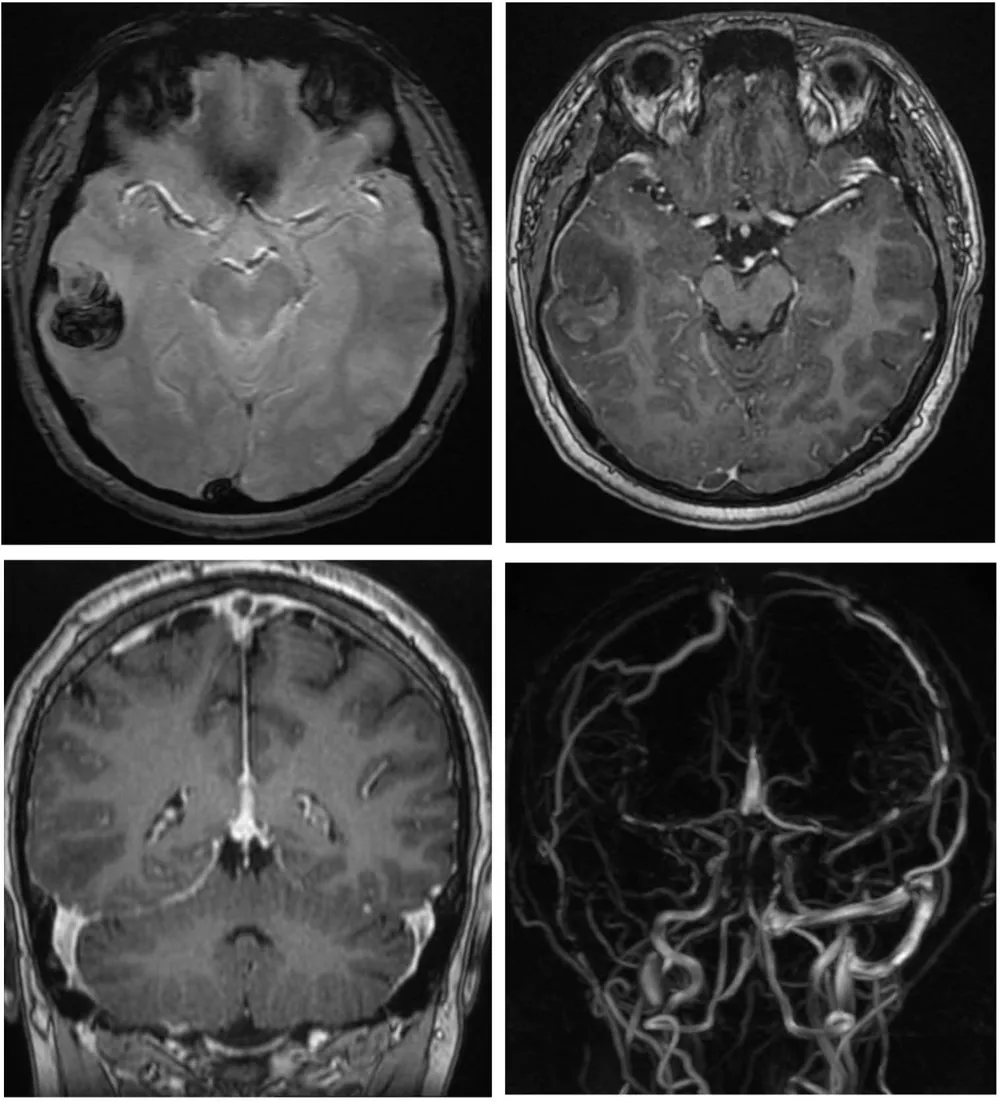

Bệnh nhân nhập viện trong tình trạng đau đầu dữ dội. Kết quả chụp CT scan cho thấy xuất huyết não, còn chụp cộng hưởng từ có bơm thuốc phát hiện huyết khối tại nhiều vị trí trong tĩnh mạch não.

Chẩn đoán hình ảnh ghi nhận bệnh nhân xuất huyết não, huyết khối nhiều vị trí trong tĩnh mạch não